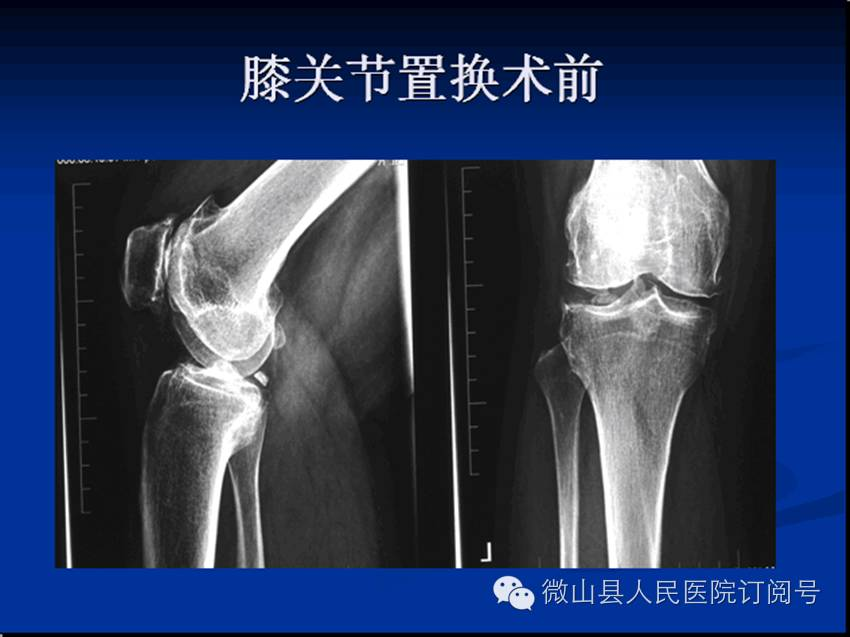

关节:主要开展微创小切口人工全髋及半髋关节置换术、人工全膝关节置换术、关节融合术。